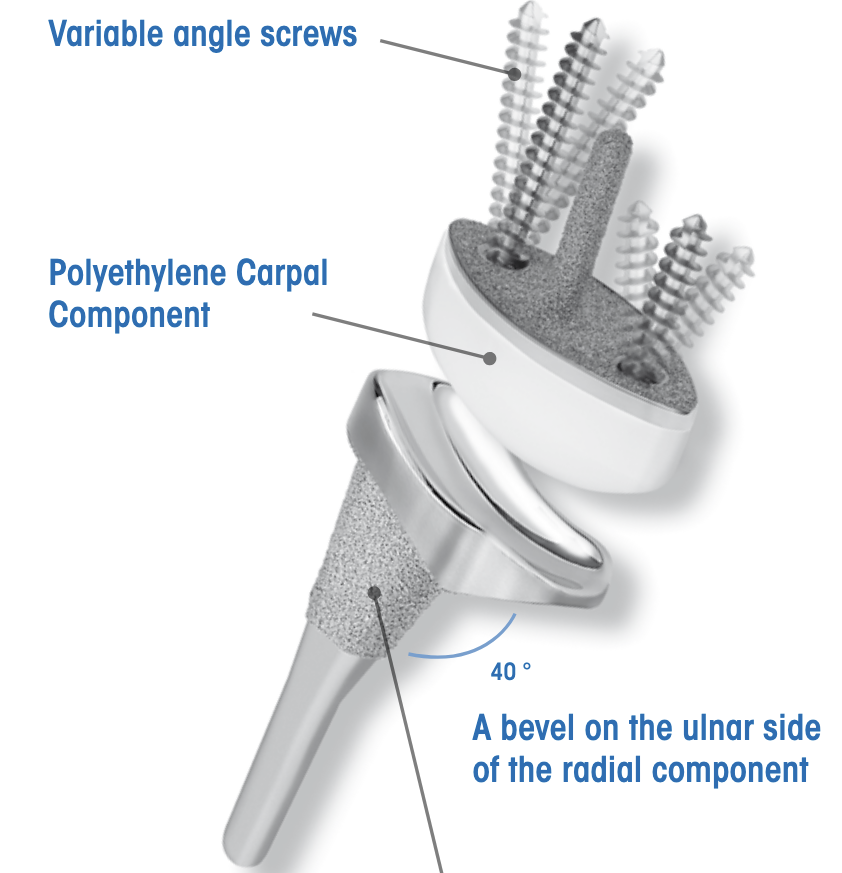

Total wrist arthroplasty

Indications

Low demand patient

Intact wrist extensors

Good bone stock

Technique

Universal 2 Total Wrist Implant system surgical technique PDF

Dorsal approach

- incision in line with 3rd meta-carpal

- divide extensor retinaculum over ECU compartment and reflect radially

- mobilize entensor tendons

- ensure ECRB and ECRL intact

- elevate wrist capsule as a distally based flap

TWA

- uncemented radial prosthesis

- excise lunate and apply carpal cutting block to capitate

- cut 1 mm hamate / capitate head / midscaphoid

- screw fixation of carpal plate

- trial polyethylene component

Results

- 425 primary total wrist arthroplasty followed for mean 2 years

- 90% inflammatory arthritis

- intra-operative fractures 2%

- postoperative fractures 2%

- 88% 10 year survival